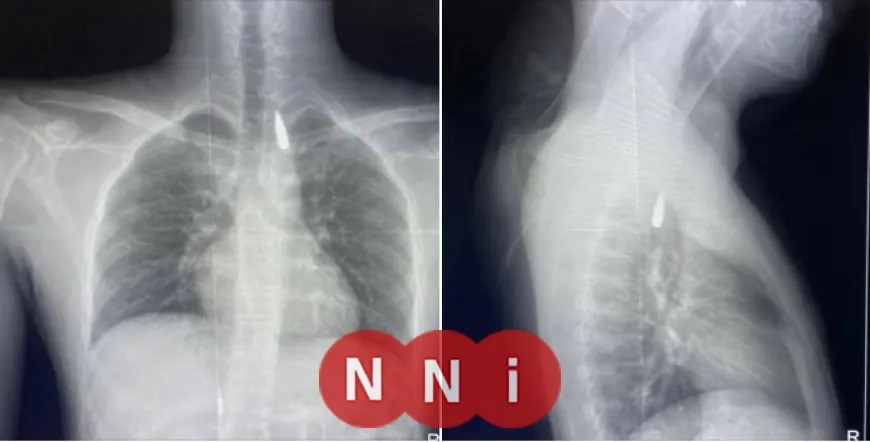

أوضح الدكتور تامر عبد الله، عميد كلية الطب ورئيس مجلس إدارة المستشفيات الجامعية، تفاصيل الجراحة التي أُجريت في 21 أكتوبر 2025.

حيث تعرض المريض لإصابة نتيجة طلق ناري في الرأس، وأدى ذلك إلى استقرار المقذوف داخل تجويف القفص الصدري، بالقرب من الشريان الأورطي، الذي يُعتبر من أبرز الشرايين في الجسم.

رغم خطورة وتعقيد الحالة، استطاع فريق من أطباء قسم جراحة القلب والصدر والتخدير بالتعاون مع معاونيهم إجراء عملية نادرة استمرت عدة ساعات في المستشفى الجامعي الجديد، حيث نجحوا في استخراج المقذوف بأمان.